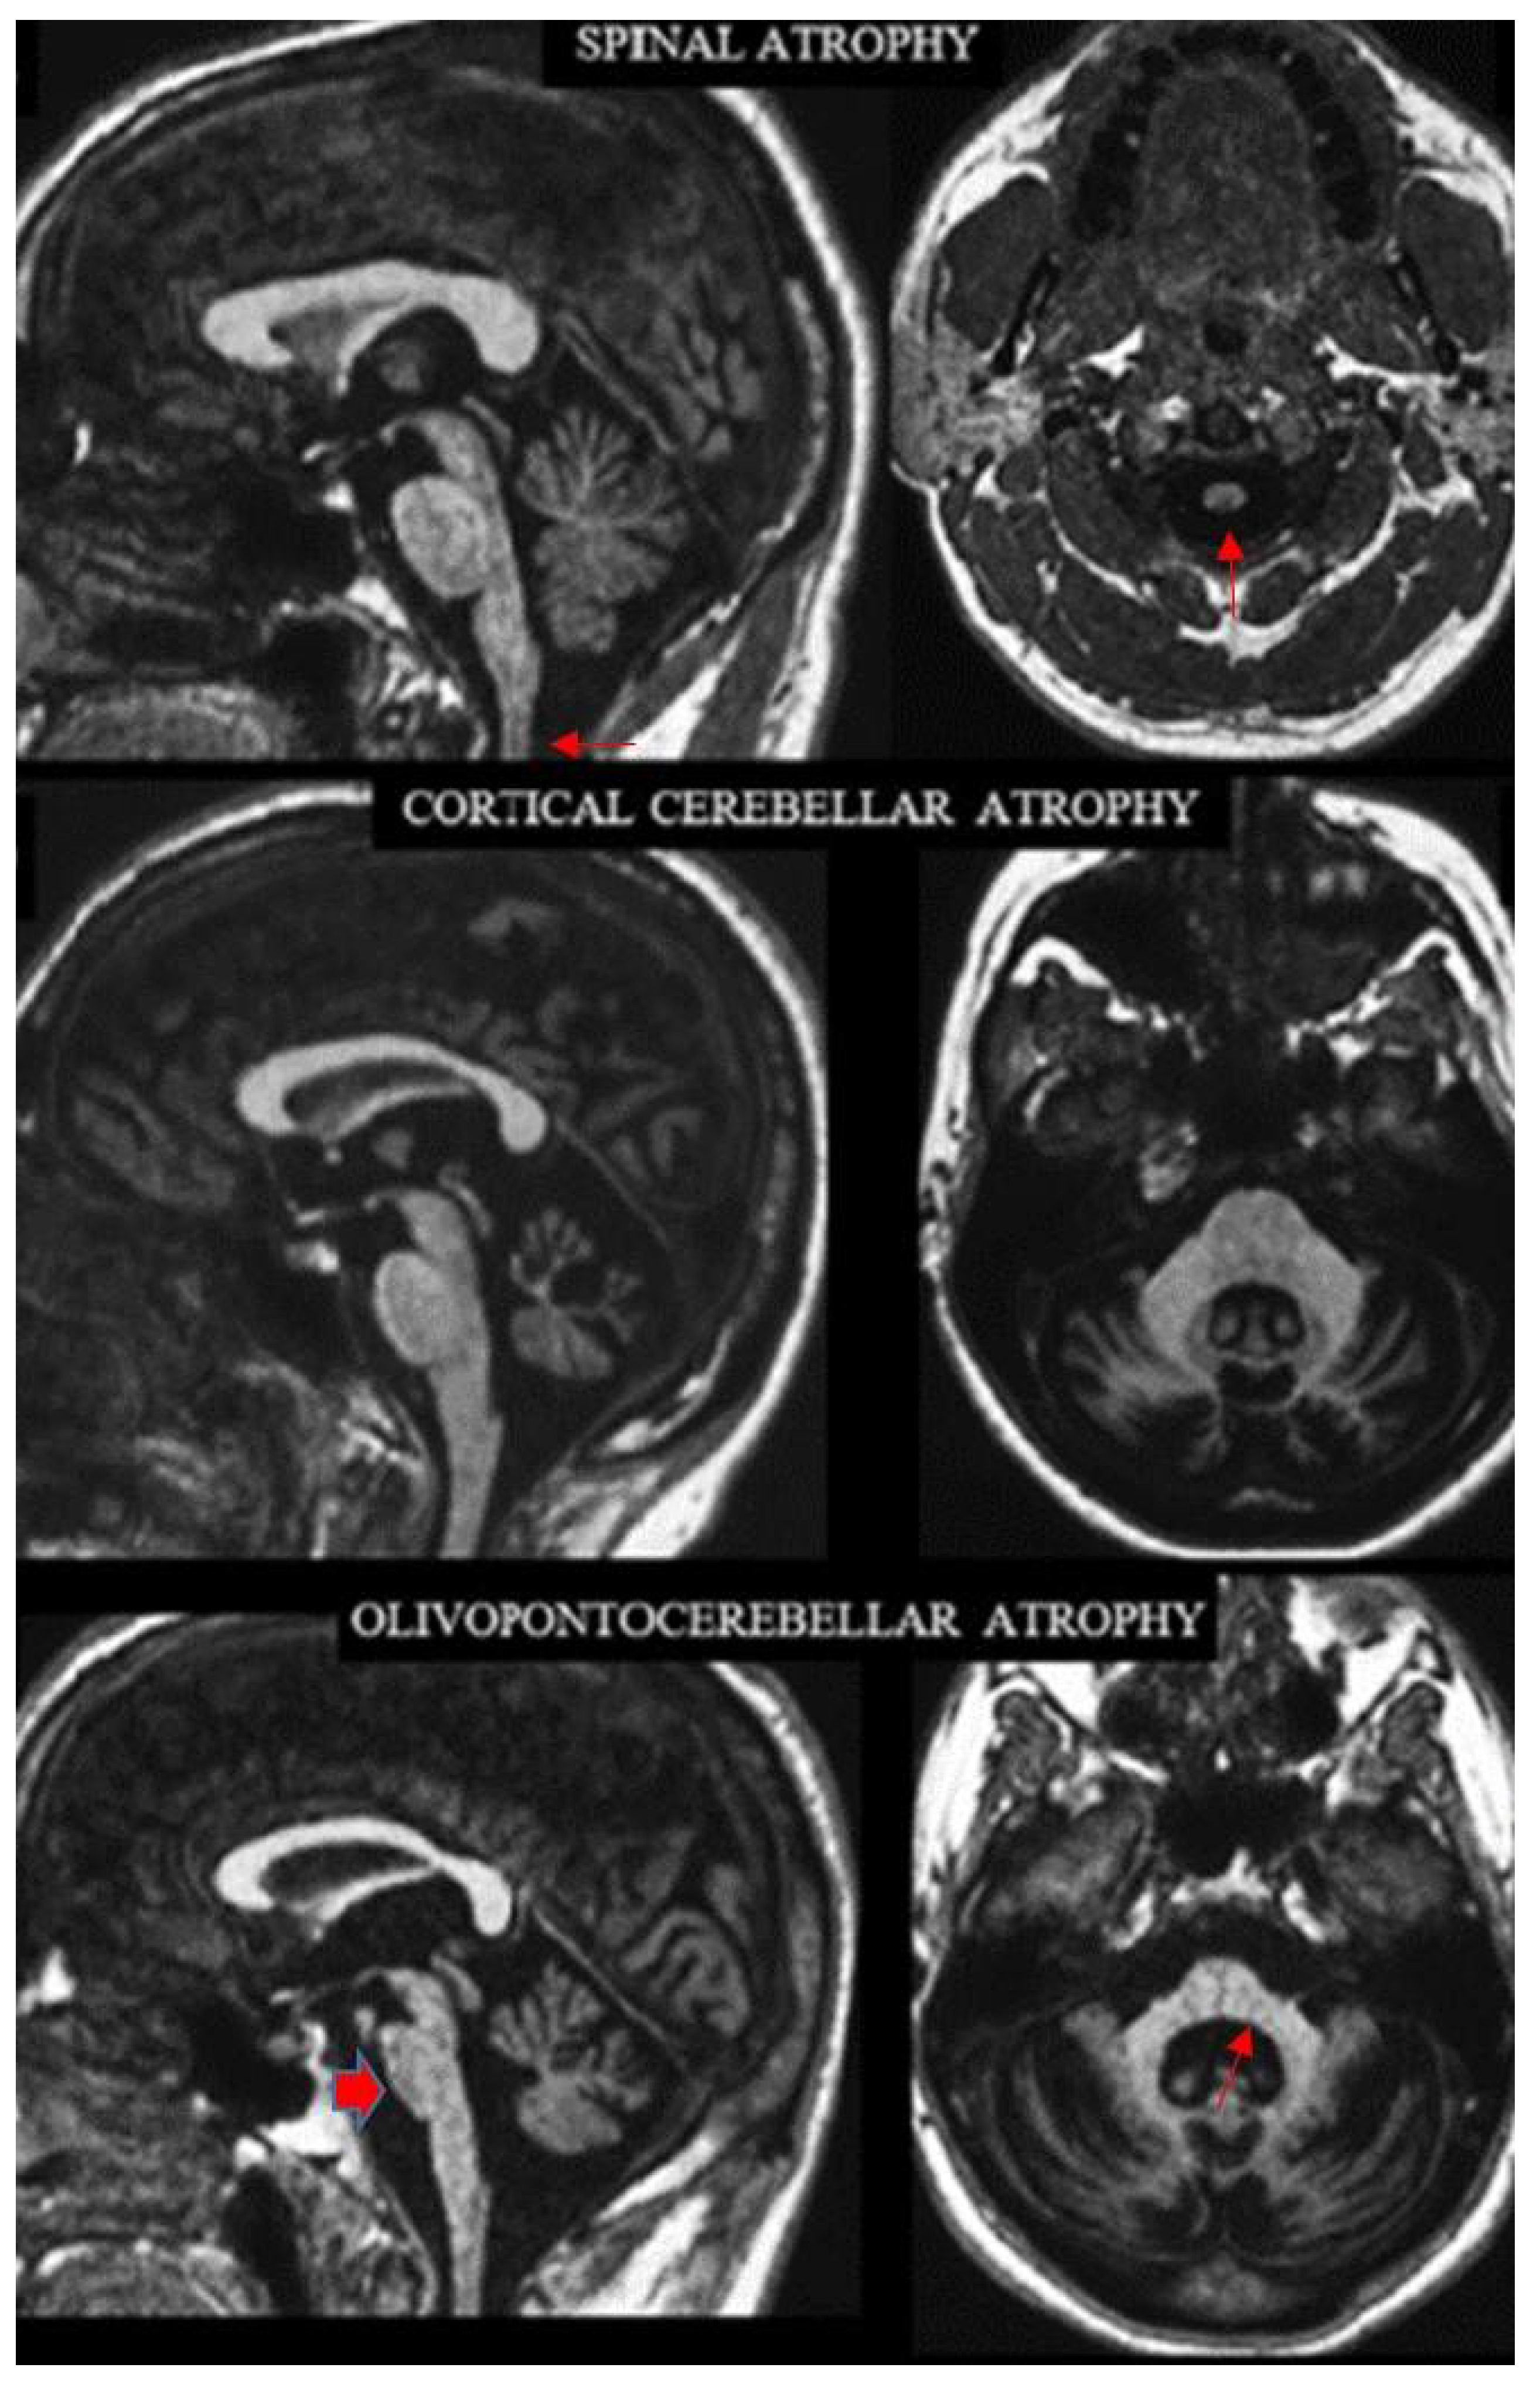

2.2. Definition of the Archetypes on MRI

- Savoiardo, M.; Strada, L.; Girotti, F.; A Zimmerman, R.; Grisoli, M.; Testa, D.; Petrillo, R. Olivopontocerebellar atrophy: MR diagnosis and relationship to multisystem atrophy. Radiology 1990, 174, 693–696. [Google Scholar] [CrossRef]

- Mascalchi, M.; Salvi, F.; Piacentini, S.; Bartolozzi, C. Friedreich’s ataxia: MR findings involving the cervical portion of the spinal cord. AJR Am. J. Roentgenol. 1994, 163, 187–191. [Google Scholar] [CrossRef]